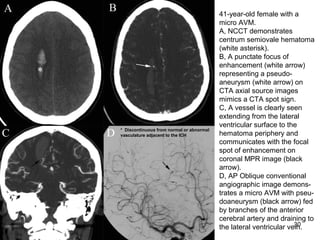

41-year-old female with a

micro AVM.

A, NCCT demonstrates

centrum semiovale hematoma

(white asterisk).

B, A punctate focus of

enhancement (white arrow)

representing a pseudo-

aneurysm (white arrow) on

CTA axial source images

mimics a CTA spot sign.

C, A vessel is clearly seen

extending from the lateral

ventricular surface to the

hematoma periphery and

communicates with the focal

spot of enhancement on

coronal MPR image (black

arrow).

D, AP Oblique conventional

angiographic image demons-

trates a micro AVM with pseu-

doaneurysm (black arrow) fed

by branches of the anterior

cerebral artery and draining to

the lateral ventricular vein.

* Discontinuous from normal or abnormal

vasculature adjacent to the ICH